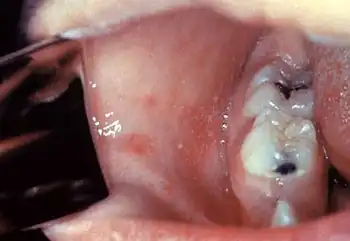

Koplik's spots seen inside the mouth are diagnostic for measles, but are temporary and therefore rarely seen.[31] Koplik spots are small white spots that are commonly seen on the inside of the cheeks opposite the molars.[30] They appear as "grains of salt on a reddish background."[32] Recognizing these spots before a person reaches their maximum infectiousness can help reduce the spread of the disease.[33]

Typically, clinical diagnosis begins with the onset of fever and malaise about 10 days after exposure to the measles virus, followed by the emergence of cough, coryza, and conjunctivitis that worsen in severity over 4 days of appearing.[63] Observation of Koplik's spots is also diagnostic.[33] Other possible condition that can result in these symptoms include parvovirus, dengue fever, Kawasaki disease, and scarlet fever.[64] Laboratory confirmation is, however, strongly recommended.[65]